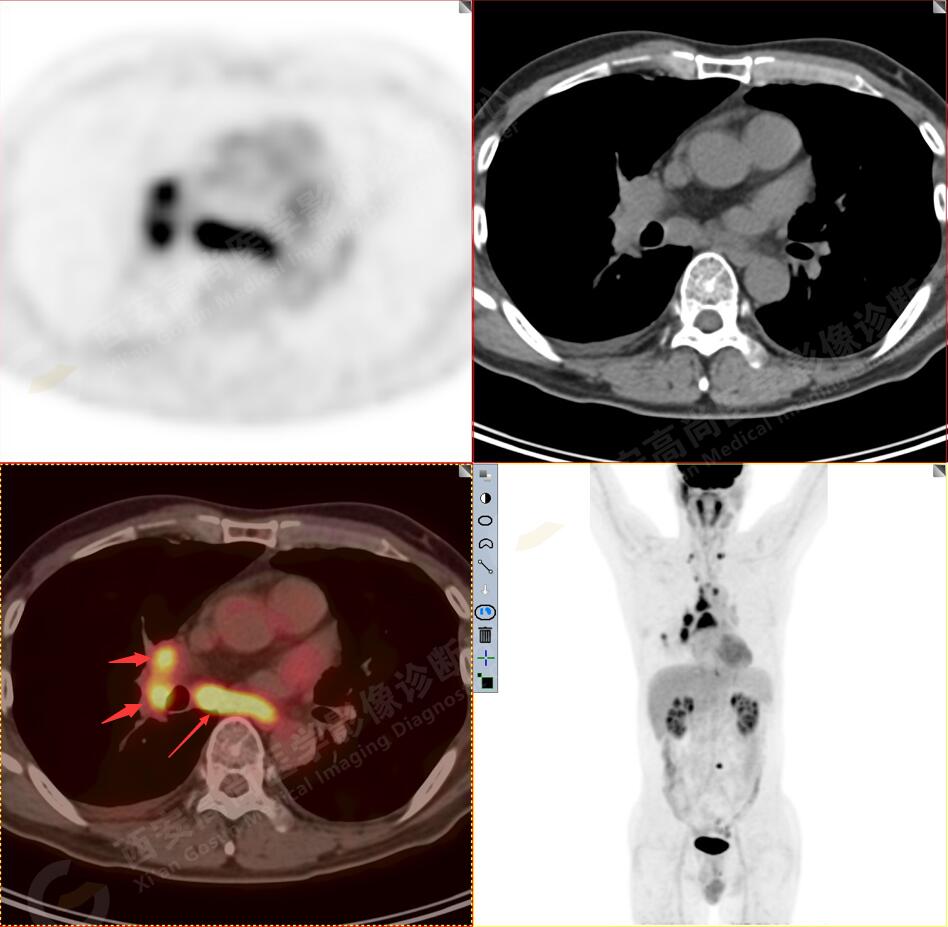

2.以下為全身多發(fā)轉(zhuǎn)移灶

3.右側(cè)肺門、縱隔(1L、1R、3A、4、6、7組)及雙側(cè)鎖骨上多發(fā)腫大淋巴結(jié),呈不同程度FDG代謝異常增高,考慮為淋巴結(jié)轉(zhuǎn)移。

4.右后胸膜輕度增厚,形成多個(gè)條狀軟組織病變,呈FDG代謝輕度異常增高,考慮為轉(zhuǎn)移性病變;右側(cè)胸腔微量積液。